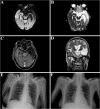

SARS-CoV-2, a novel zoonotic coronavirus, is currently spreading all over the world, causing a pandemic disease defined coronavirus disease 2019 (COVID-19). The spectrum of COVID-19 ranges from asymptomatic or mild infection to rapidly progressive, acute respiratory distress syndrome and death [1].To the best of our knowledge, status epilepticus has never been described as initial presentation of COVID-19. We report a patient affected by COVID-19 whose primary presentation was a focal status epilepticus.